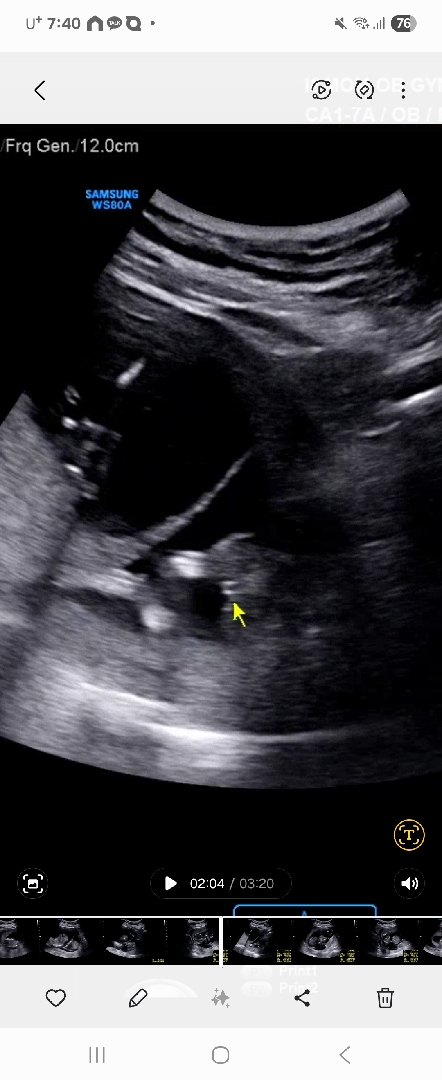

15주

이정도면 아들일가요?

끝이 갈라지면 딸이라던데..! 15주시면 선생님이 말씀 안해주시던가요ㅎㅎㅎ

네 안해주셨어요 ㅠㅠ모르겠다구